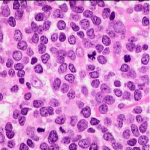

I ricercatori della UT Southwestern Medical Center hanno identificato un gene specifico che regola la capacità del cuore di rigenerarsi dopo le lesioni.

Nel 2011, il laboratorio del Dott. Sadek ha dimostrato che il cuore dei mammiferi neonati è capace di una risposta rigenerativa vigorosa al danno, attraverso la divisione delle proprie cellule. Come si sviluppa il neonato, il cuore perde rapidamente la capacità di rigenerarsi e di riparare le lesioni provocate da attacchi di cuore, ad esempio.

Il gruppo di ricerca ha dimostrato che la soppressione di Meis1 ha esteso il periodo di proliferazione nei cuori dei topi neonati e ha anche ri-attivato il processo rigenerativo nel cuore adulto del topo, senza effetto nocivo sulle funzioni cardiache.Questa nuova scoperta dimostra che Meis1 è un fattore chiave nel processo di rigenerazione e la comprensione della funzione del gene può portare a nuove opzioni terapeutiche per la rigenerazione del cuore adulto. I risultati forniscono anche una possibile alternativa alla attuale ricerca sulla rigenerazione del cuore nell’adulto,  che si concentra sull’uso di cellule staminali per sostituire le cellule cardiache danneggiate.